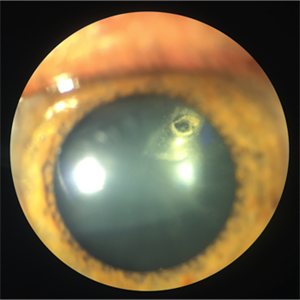

Subluxated cataract

Jan 6 2018 by Andrea Arriola-Lopez, MD MSc

72-year-old man with bilateral progressive visual loss. Subluxated cataract was found in OD. Lensectomy and vitrectomy will be done.

Photographer: Andrea E. Arriola-López MD MSc

Condition/keywords: diabetes, subluxation of lens